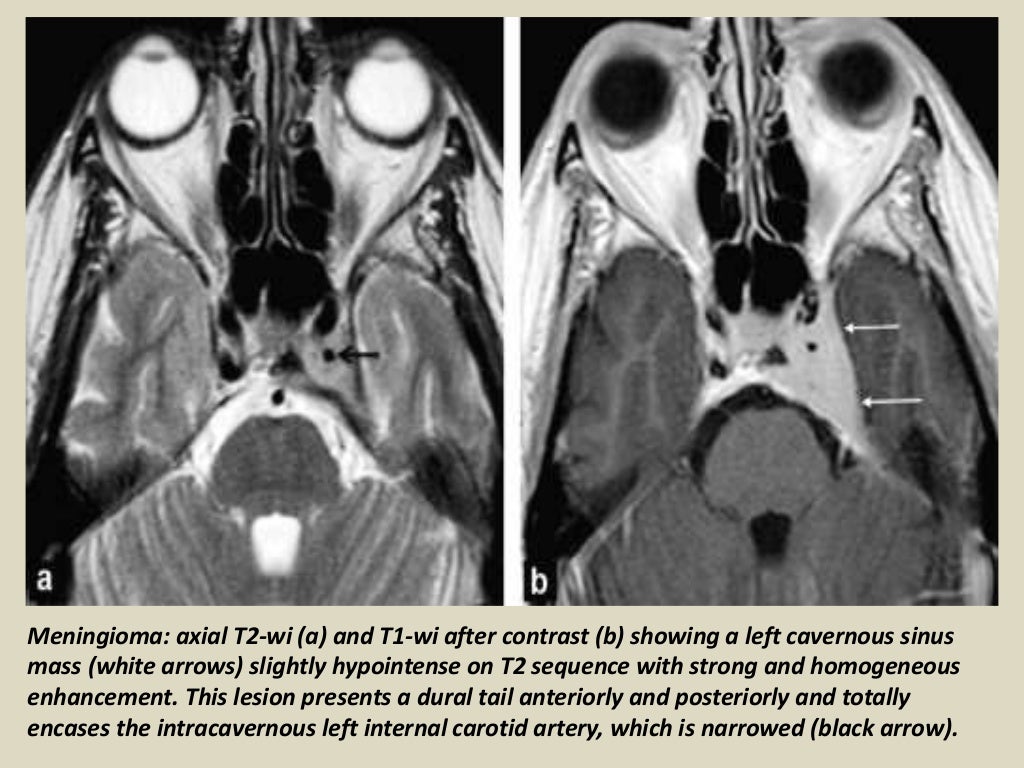

Presentation1, radiological imaging of cavernous sinus lesions. Mri Anatomy Cavernous Sinus The purpose of the article is to (a) describe the anatomy of the cavernous sinus; The main purpose of this pictorial review is to highlight the important mr imaging findings of various conditions involving the cavernous. It plays a crucial role in the. The purpose of this article was to review the. The cavernous sinus is a paired, venous structure. Mri Anatomy Cavernous Sinus.